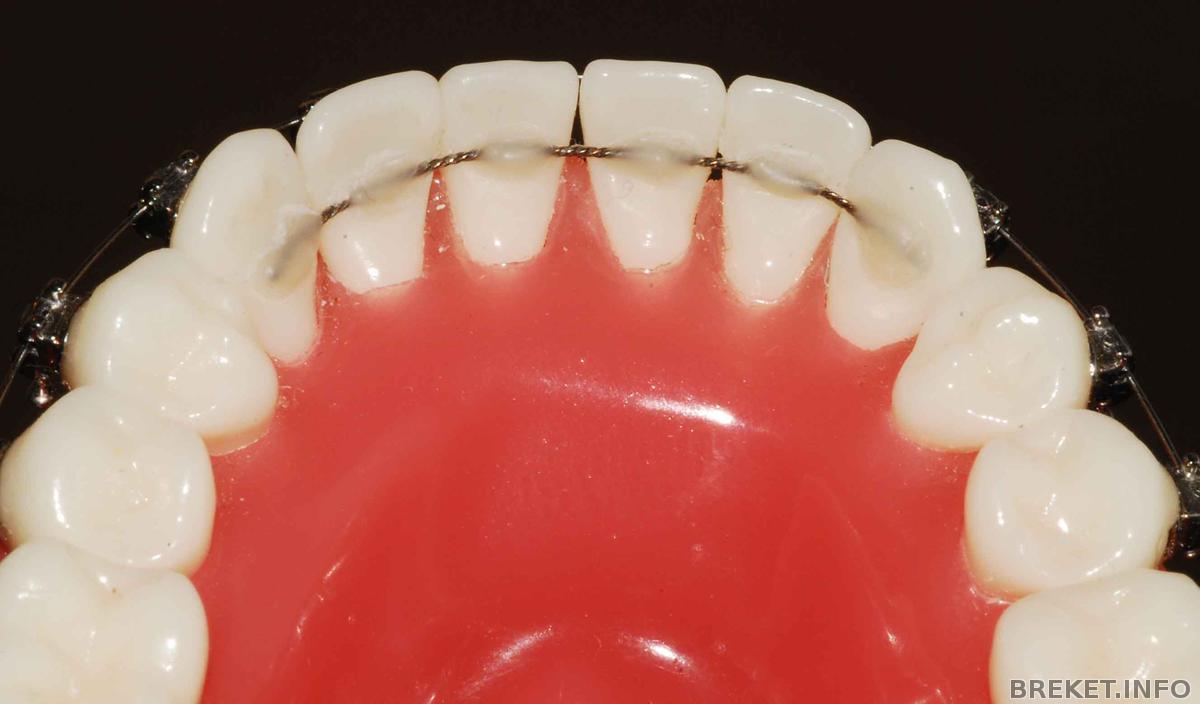

ДИАГНОСТИЧЕСКИЕ МОДЕЛИ — Модели зубов пациента, отлитые из гипса по индивидуальному слепку. Являются точной объемной копией верхних и нижних зубов пациента. Необходимы для геометрических измерений и определения смещения зубов относительно ориентиров, а так же для подбора элементов брекет-системы.

СЛЕПКИ — Точные оттиски зубных рядов пациента, которые получают с помощью специальных быстротвердеющих пластических материалов. По слепкам отливаются гипсовые модели челюстей, которые в ортодонтии необходимы для диагностики или изготовления ортодонтической аппартуры.